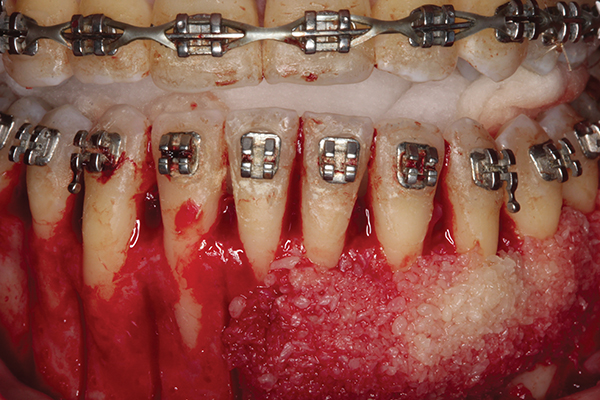

Fig 3. Corticotomy cuts performed.

Figure 3